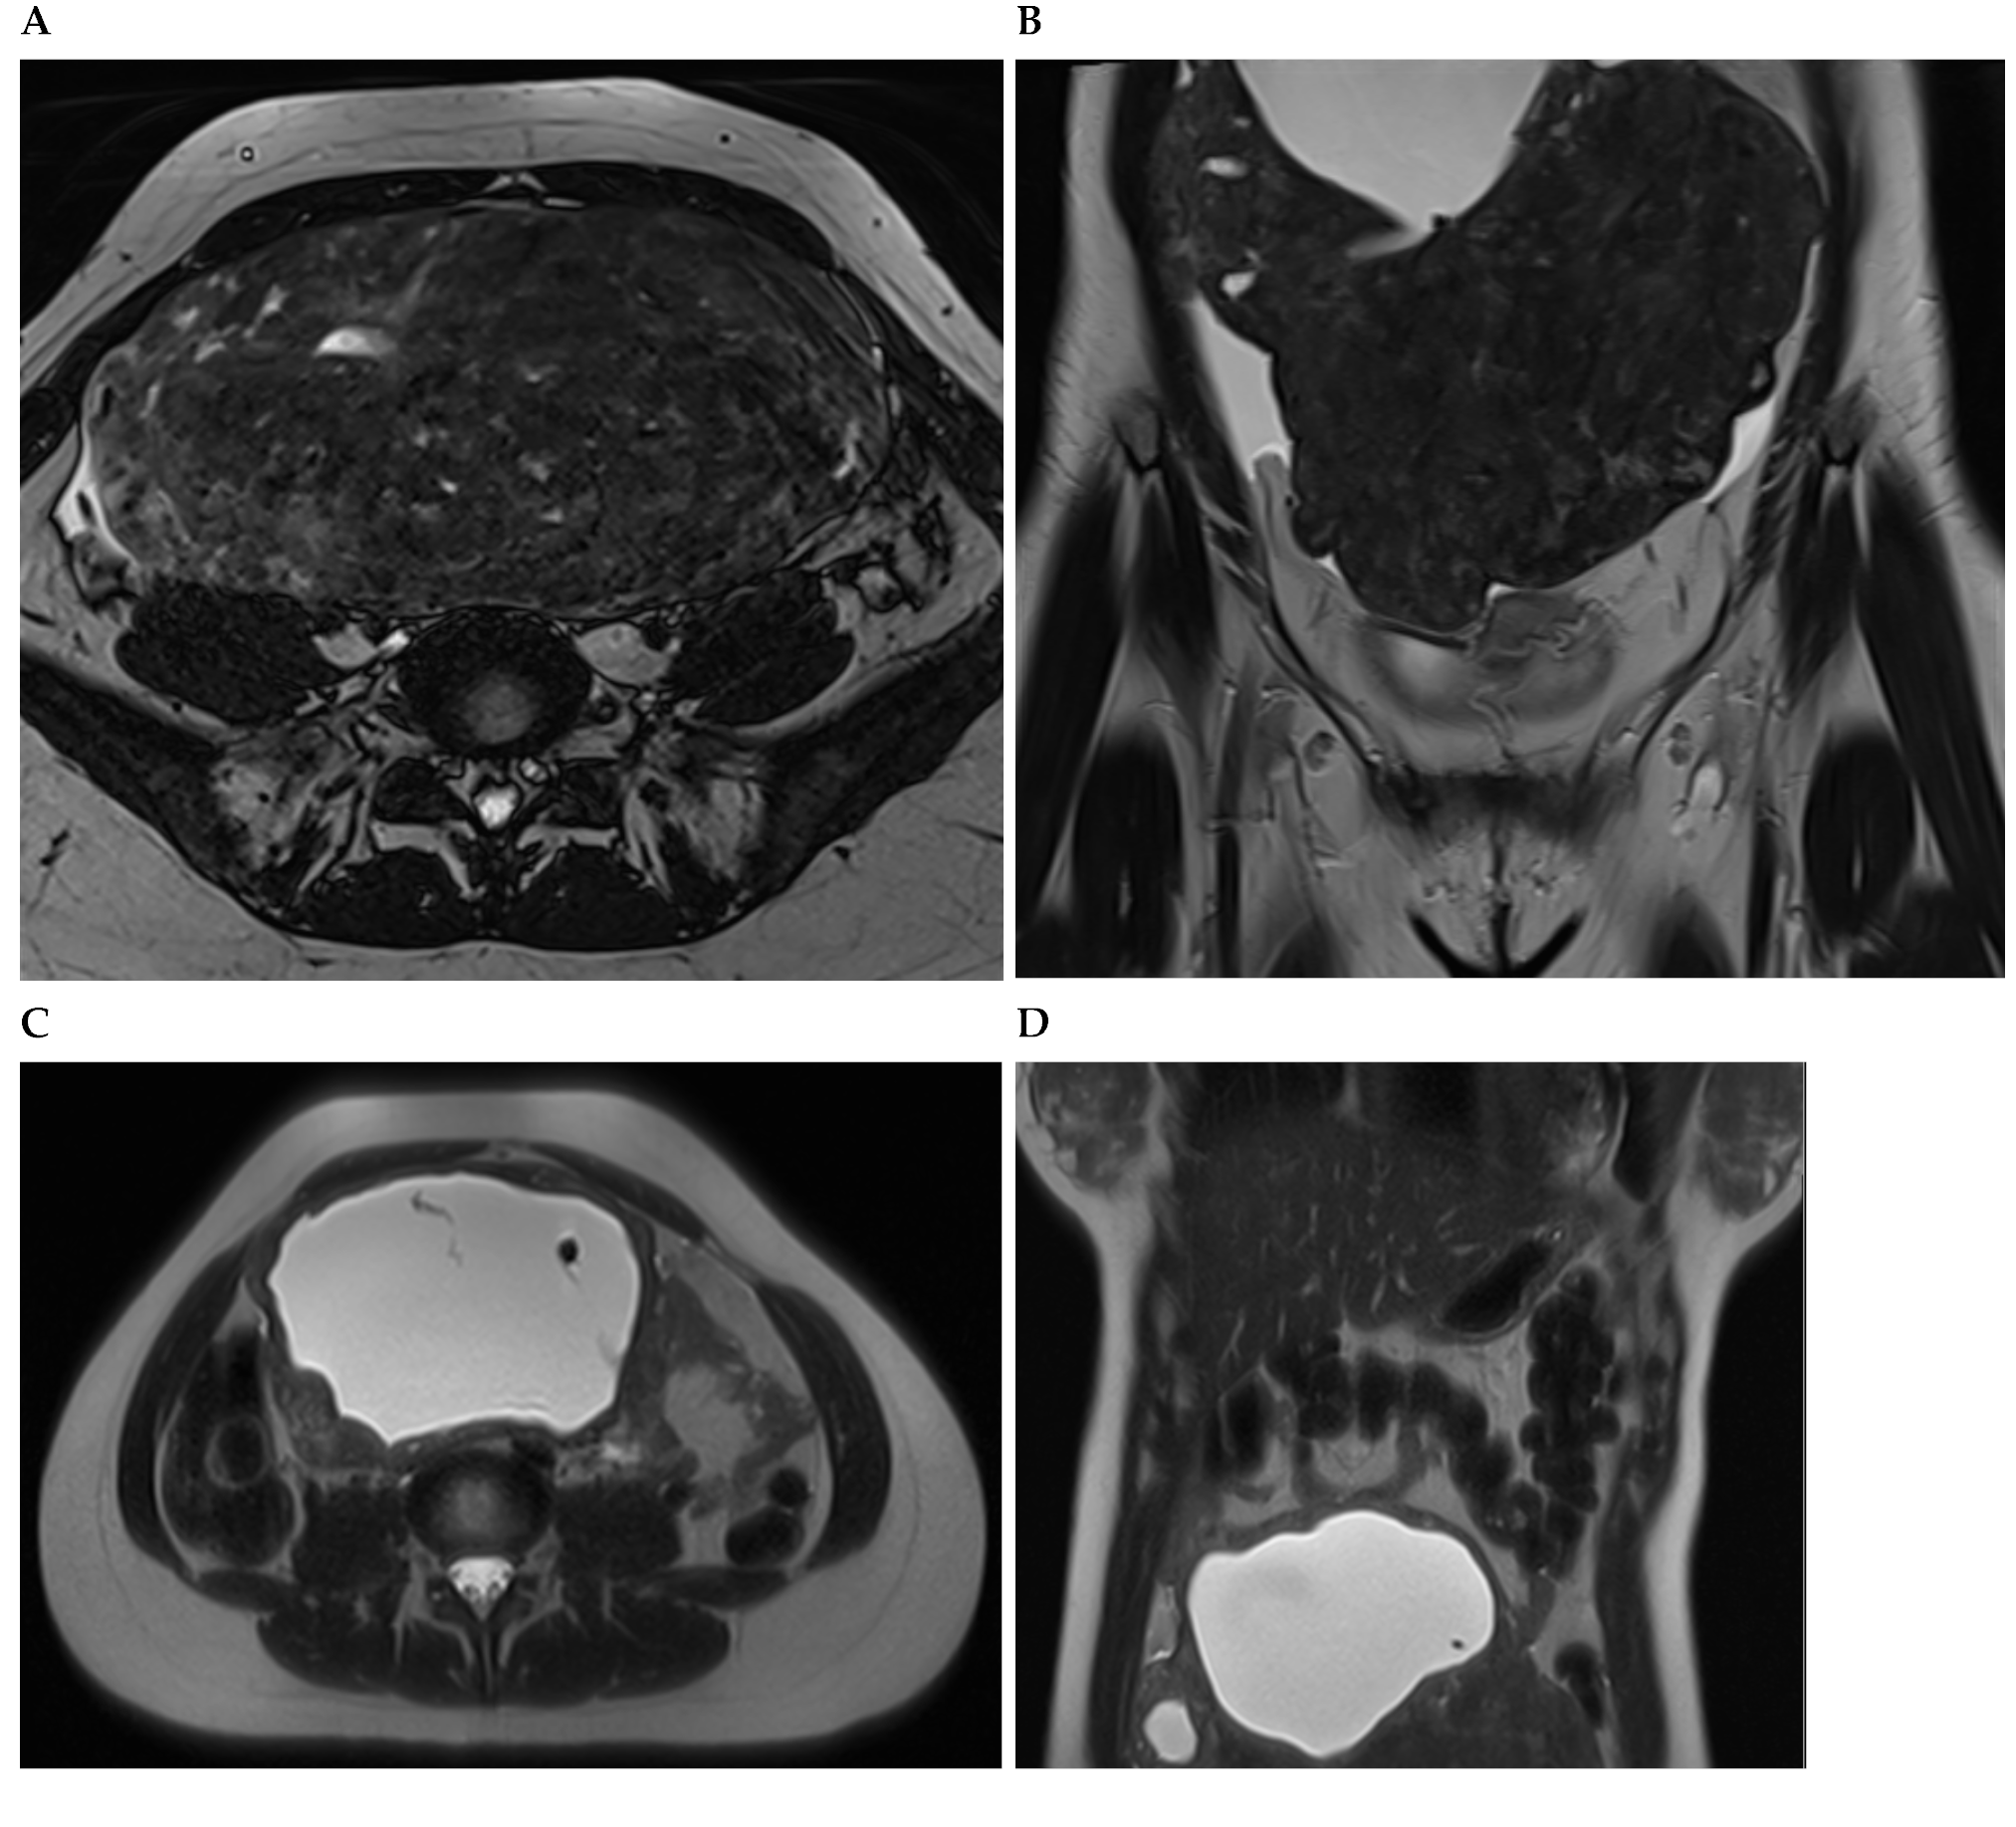

Figure 3. A woman with non-oral contraceptive user, presented to the outpatient clinic requesting a second opinion concerning a 240 mm sized uterine leiomyioma found by ultrasound at a different healthcare center. A computed tomography showed a uterine multinodular lesion with signs of degeneration. The patient received magnetic resonance imaging examination (Figure 3) and surgery with total myomectomy and specimen histopathological analyses (Figure 4). Herein, Figure 3 shows a subserosal-pedunculated leiomyoma with hyaline and cystic degeneration in a 29-year-old woman. (A) Axial and (B) coronal T2-weighted (T2) Dixon magnetic resonance imaging (MRI) showed a normal-sized uterus with axial organ rotation by 180° in an anticlockwise direction. From the right cornual region of the uterus, there was a low signal intensity (T2) subserosal-pedunculated mass (FIGO 7). This well-circumscribed, giant abdominopelvic mass measured approximately 173 × 84 × 174 mm and presented signs of cystic degeneration on its most cranial portion by demonstrating an internal, round, well-defined area with homogeneous fluid-like high signal intensity (T2), best represented on (C) axial and (D) coronal T2 half-Fourier acquisition single-shot turbo spin-echo MRI. It also demonstrated (E) low-signal intensity on non-contrast axial T1-weighted (T1) Dixon MRI, (F) without enhancement on arterial axial T1 Dixon MRI, further suggesting cystic degeneration (up to 80% of histological distribution of degeneration area) of this giant leiomyoma.